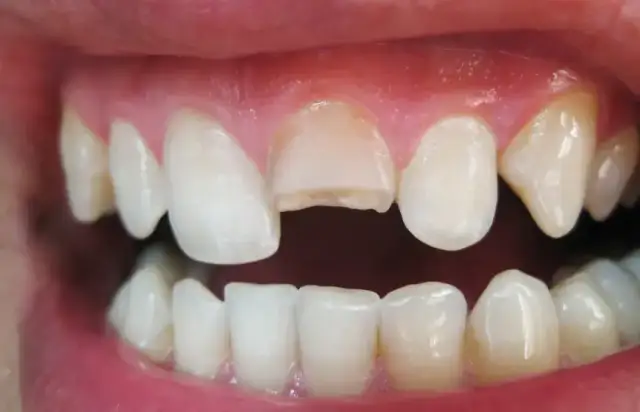

Kolejnym częstym problemem jest zbyt silne szczotkowanie zębów. Używanie nadmiernej siły, zwłaszcza twardą szczoteczką, może prowadzić do mechanicznych uszkodzeń szkliwa, odsłonięcia szyjek zębowych, a w konsekwencji do nadwrażliwości zębów i recesji dziąseł, czyli cofania się linii dziąseł. Pamiętaj, że delikatność i precyzja są kluczowe.